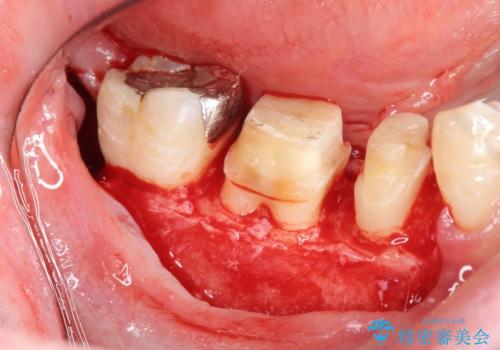

深い虫歯 セラミッククラウンの精度を高める歯周外科手術

マイクロスコープを用いた根管治療を行ったのち、深い虫歯に起因する歯ぐきの腫れ・出血を改善すべく歯周外科を行いました。

歯周組織が落ち着くのを待ち、セラミッククラウンで機能・審美性を改善します。

歯内・歯周環境が整備されたことで長期的な予後の期待できるセラミック治療を行うことができました。